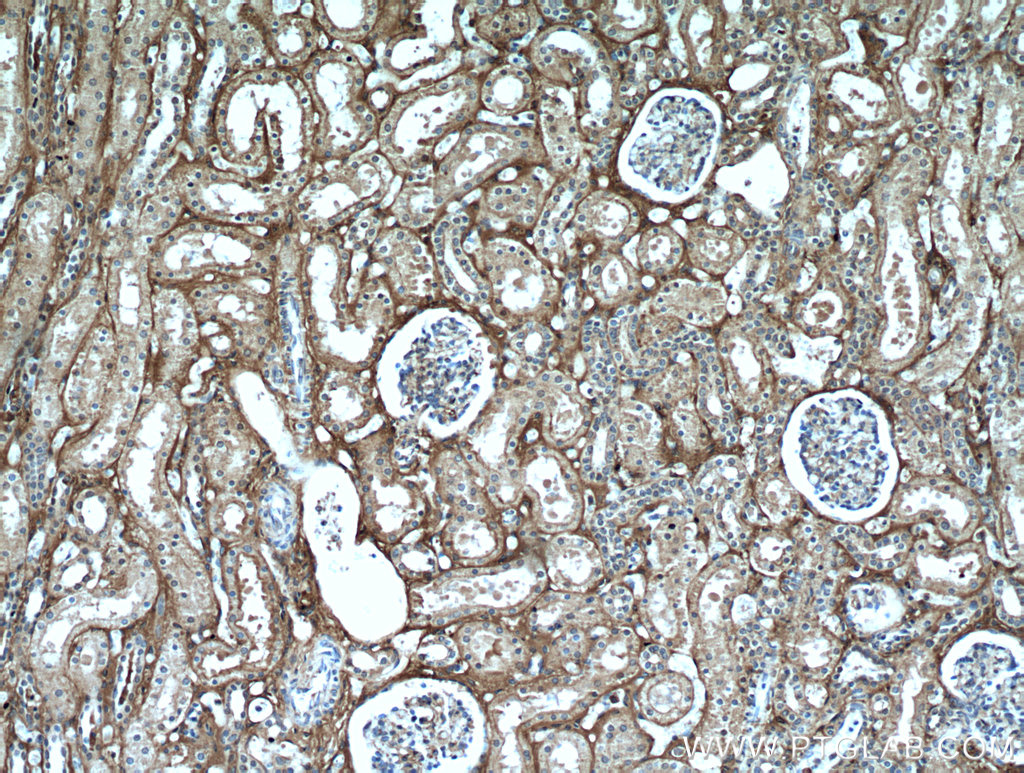

使用范围: WB,ELISA,IHC-P,IHC-F,IF